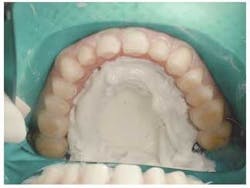

Upon anesthetizing the patient, I decided to remove the old veneers to observe the underlying teeth. I was able to observe the old preparations and the actual color of the teeth. This information will help me with my new preparations (Fig. 6).

null

We found some severely tetracycline-stained teeth that had hardly any preparation. The result was thick teeth (Fig. 7). This is the main reason the ceramist was not able to correct many of the nuances of the smile design we discussed earlier. Adequate preparation is the only way to obtain a fantastic result.